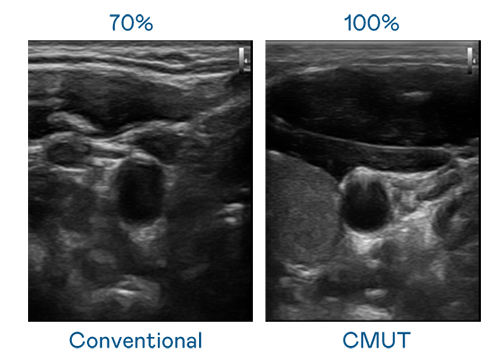

CMUT 技术是一种用电容式微机电元件来产生超音波讯号的技术。与传统 PZT 压电式技术相比,CMUT 频宽增加 30%,更宽频的超音波讯号让影像解析度大幅提升,是实现高影像品质医疗超音波扫描、促进精准医疗发展的关键技术。

大频宽带来超清晰影像

超音波影像的解析度高低,首先取决于探头能发出的讯号频宽。PT视讯(中国区)官网 CMUT 可提供高清晰的超音波讯号,提供高频宽、高灵敏度、影像纹理细节更高的超音波影像,协助医护人员缩短影像判读时间及利用精准的医疗影像进行诊断。